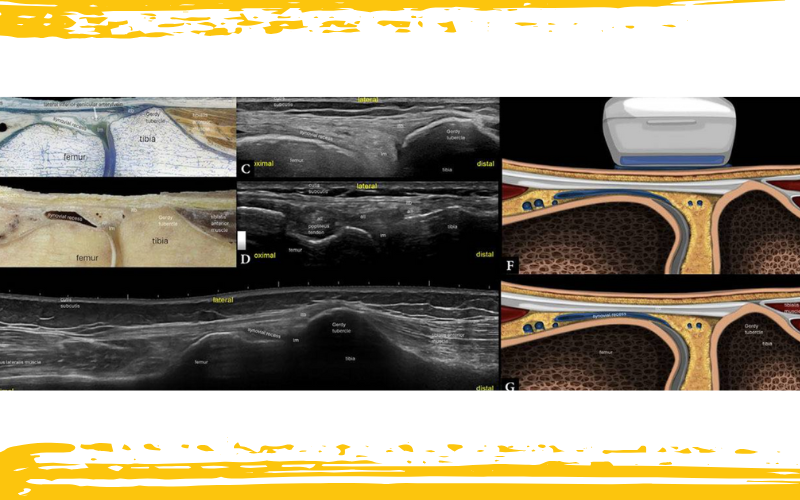

Rodilla lateral. Imágenes histológicas (A), anatómicas (B) y ecografías longitudinales (C–E). Ilustraciones con la posición de la sonda en plano longitudinal suprarrotuliano (F–G).

En C, se muestra el eje largo de la banda iliotibial distal (ITB) en su inserción en la tuberosidad de Gerdy.

En D, la parte distal de la sonda permanece casi fija, mientras que la parte proximal se rota cerca de la inserción del ligamento colateral lateral, para visualizar una fina estructura ligamentosa: el ligamento anterolateral (ALL).

E. Imagen longitudinal con campo de visión extendido de la parte distal lateral del muslo y la parte proximal de la pierna.

lm – menisco lateral.